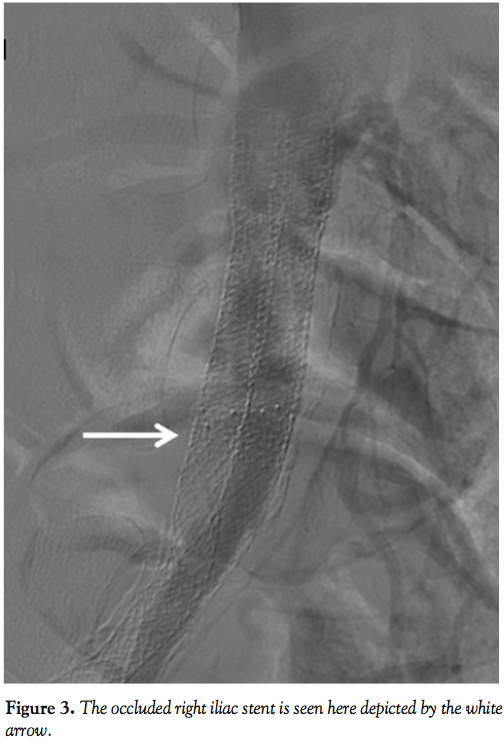

try a retrograde approach using a 6 Fr sheath in the right common femoral artery. The difficulty was due to the fact that our wires kept going into the left iliac through the juxtaposed stents in the distal aorta. It was then decided to use a 10 cm Trellis device for pharmacomechanical thrombectomy. During this, an 8.0 x 120 balloon was inflated in the distal aorta to the left common iliac artery juxtaposed stent to prevent the embolization of thrombus and to keep this isolated to the left lower extremity (Figure 4). A total of 20 mg of tissue plasminogen activator was used with good results, after which kissing-balloon inflation was performed in the distal aorta to the bilateral common iliacs. Final angiogram (Figure 5) showed good flow in bilateral iliac arteries with 3-vessel runoff to both feet.